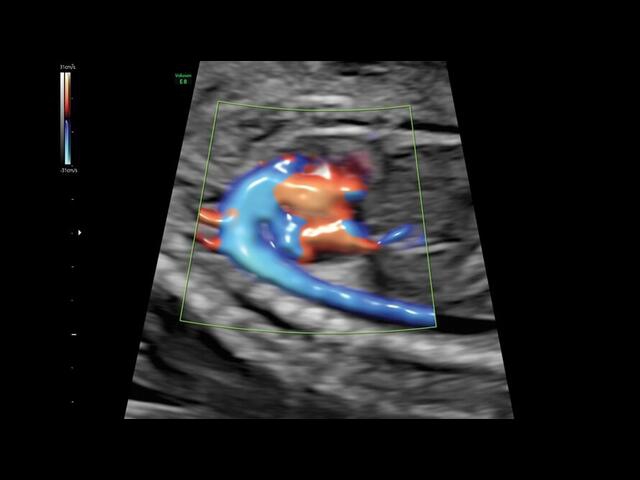

Система GE Voluson E8 обладает значительной вычислительной мощностью, которая позволяет решать даже самые сложные задачи в области диагностики плода. Она отличается высоким уровнем качества и статусом, предоставляя врачу потрясающие изображения во время 2D/3D-исследований. Кроме того, система всегда готова к использованию режима 4D благодаря чувствительному цветному доплеру.

• HD-FlowTM для точного изучения кровотока и прорисовки сосудов.

Трехмерная реконструкция ЦДК:

Да